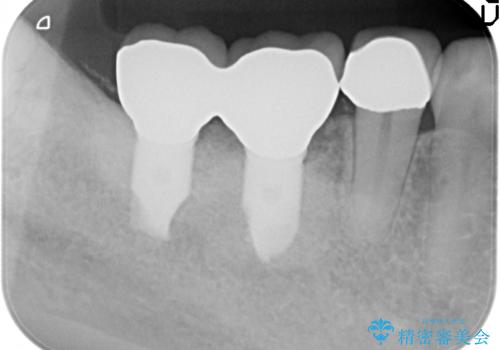

- 前歯の変色の改善を希望され来院されました。

神経の失活による歯の変色、虫歯治療後によるコンポジットレジンの経年変化変色がみられたので全体をセラミックで覆うオールセラミッククラウン治療を計画します。

歯の神経が失活に根管治療を行い時間が経つと色調の変化が現れます。コンポジットの充填量も大きく経年劣化している場合全て取り除いたのちオールセラミッククラウン治療をお勧めいたします。